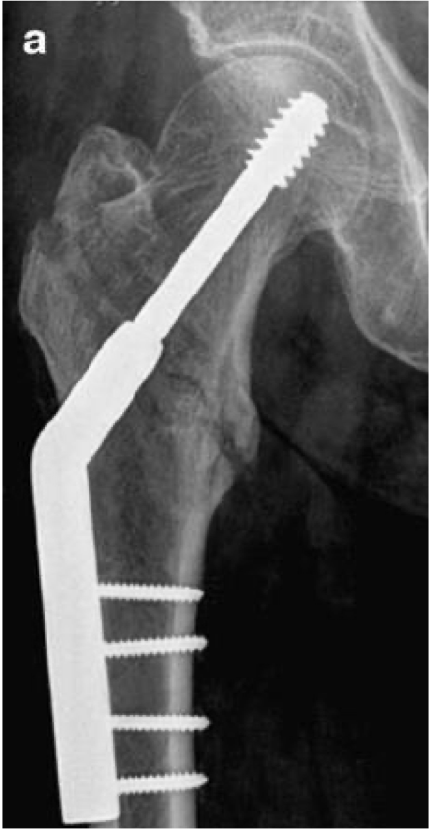

when do you use a dynamic hip screw?

-intertrochanteric fractures

New cards

what are the beneftis of a hip screw?

-allows for sparing of the femoral head

-keep normal hip mechanics

what is a dynamic hip screw?

large screw with side plate and several small screws

<p>large screw with side plate and several small screws</p>